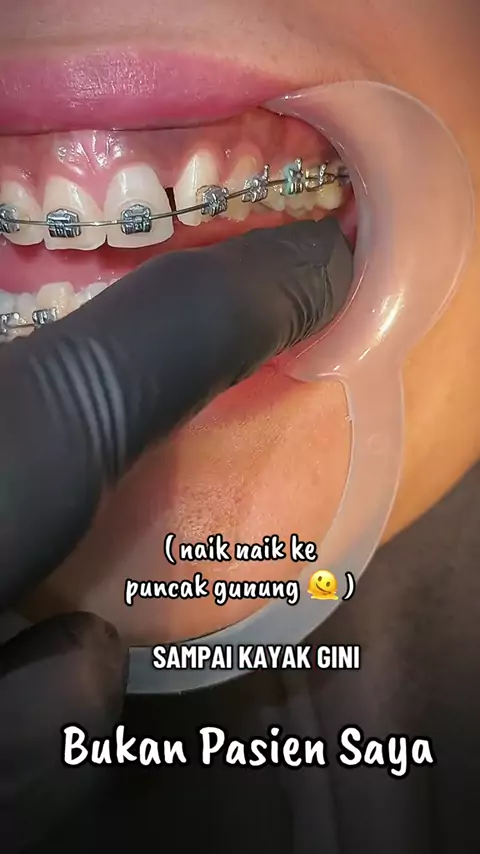

Risk it All... Risk all the cases Brain training Thinking Put it on Move it slowly With my mind and heart Still 3 times Need more but wish not that long Ambil Risiko Semuanya... Ambil risiko semua kasus Latihan otak Berpikir Insersi Gerakkan perlahan Dengan pikiran dan hatiku Masih 3 kali Butuh lebih banyak tapi berharap tidak lama lama I Wish I Pray Good night 🌹 Swet Dream drg. Silvia. Sp. Ort#behel#behelgigi#progress#orthodontist#

HARI INI (Kontrol Ke 4 ) Maloklusi kelas 1, gigi atas dan bawah berdesakan. Pergerakan pelan pelan saja dan semakin indah dalam 5 bulan, tidak terlalu lama. Masih perlu beberapa perawatan, tetapi kemajuannya nyata, perlu menemukan kunci oklusi di bagian posterior kanan. Rotasi gigi dan gigi yang berdesakan telah terkoreksi dengan baik. Alhamdulillah Y Rabb Semua ini karena tuntunanmu semata di pikiran dan hatiku, selama seluruh perawatan dan perjalanan pemasangan behel. Allah Maha Besar, Mah...

The Oclussion Kunci gigitan, kasus boderline, plek ketika digigit dan ditutup tidak ada cekah atas bawah kecuali sisa ruang sedikit untuk retraksi anterior. good night drg. Silvia. Sp. Ort #behelgigi #behelstory #orthodontist #surabaya #

Anterior Retraction with Wire Bending No need powerchain Make any kind of loop of wire bending technique Trying back doing this Boring with powerchain We could do anything with wire bending Need to learn more Need to train more I am not the expert as @Drg Paulus Maulana Sp Orto @Octavin Spesialis Orthodontist @Felix The Orthodontist I am just Bak Pia Pathok At least I am trying my best 🌹🌹 Last Night #orthodontic #orthodontist #surabaya #educatorsof #

Naik Naik ke puncak gunung Tinggi tinggi sekali Pake self ligating dibilang Cepat Hasilnya jebat kesana sini Kiri kanan kulihat gelap gelap sekali Takut takut kalo nyasar lagi Duit abis banyak sekali Salam Inget Mati drg. Silvia. Sp. Ort #behelgigi #malpractice #korban #doktergigi #